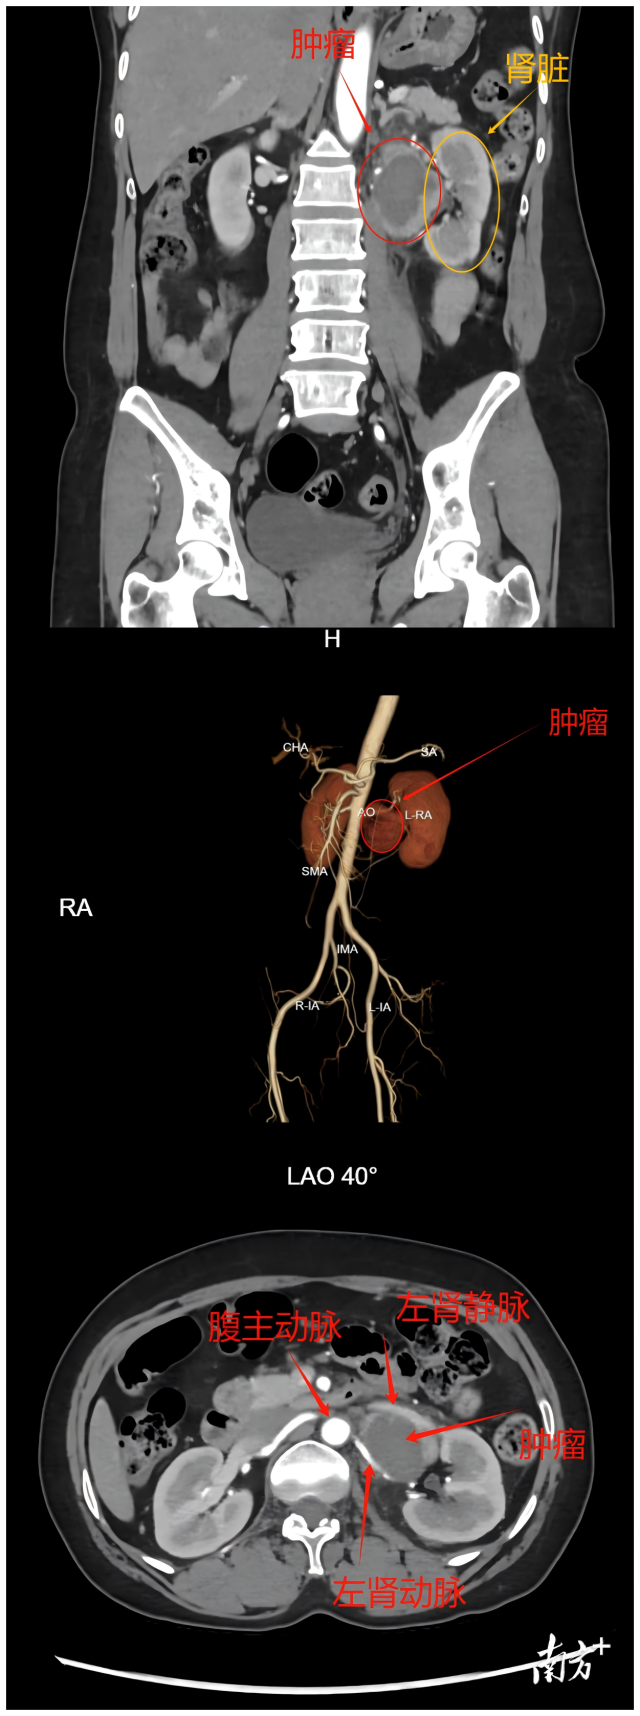

和祐醫院泌尿外科謝克基主任團隊評估發現:這個4cm的腫瘤位於解剖複雜的左腎門區,影像顯示其被多根大血管包繞。“就像在輸油管道旁拆除炸彈,”謝克基解釋,“術前CT顯示腫瘤與血管鞘界限不清,這類患者未經規範術前準備的手術死亡率可達20%-45%,甚至更高。”進一步的檢查證實,持續的高血壓已經對(化名)的心臟造成了損傷,這更增加了手術風險。面對這一複雜病例,醫院立即啟動了多學科會診機制。

腫瘤位置示意圖

經過充分準備,近日,手術如期進行。術中發現實際情況比預想的更為複雜:腫瘤大小6cm×4cm×4cm,位於左腎門區,緊貼左腎靜脈主幹、左生殖血管和左腎上腺靜脈,並與胰腺、腎上腺高度粘連。